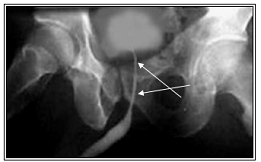

2.3 Модель имитационной ситуации при изучении темы "Гиперплазия и рак простаты - вопросы дифференциальной диагностики"